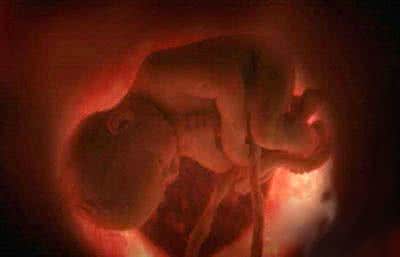

据介绍,经过中山大学法医鉴定中心鉴定,根据法医系统尸体解剖检验,邹某之女体表及内部器官未发现机械性损伤征象,故可排除机械性暴力作用致死。结合案情分析,邹某之女属未成熟儿,符合宫内窒息死亡。

对此,原告方则反驳,根据中山大学法医鉴定中心的医学鉴定显示,邹某之女的尸体体表及内部器官未发现机械性损伤征象,故可排除机械性暴力作用致死,因此可以排除与医生操作有关。不过,邹某的辩护人则认为,医学鉴定只是说排除机械性暴力作用致死,并不能排除与医生吕某某的操作有关。